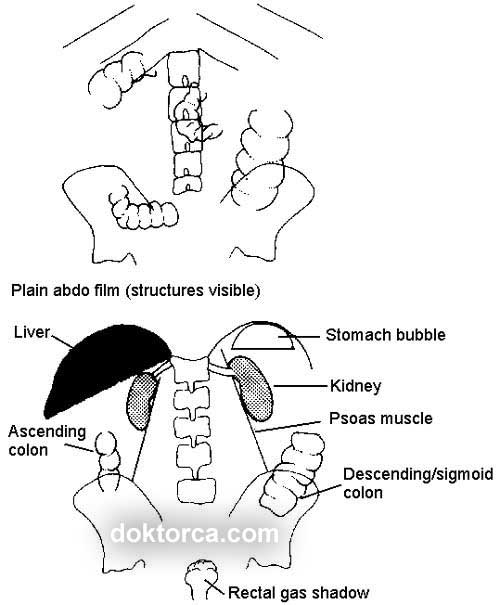

Çekim sonrası, ADBG yorumlanması çok önemlidir. Özellikle travmaya bağlı hava sıvı seviyesinin tespiti, bağırsak tıkanmaları, gazların ve yumuşak dokudaki anormal yapıların gözlemlenmesi amacı ile çekilir.